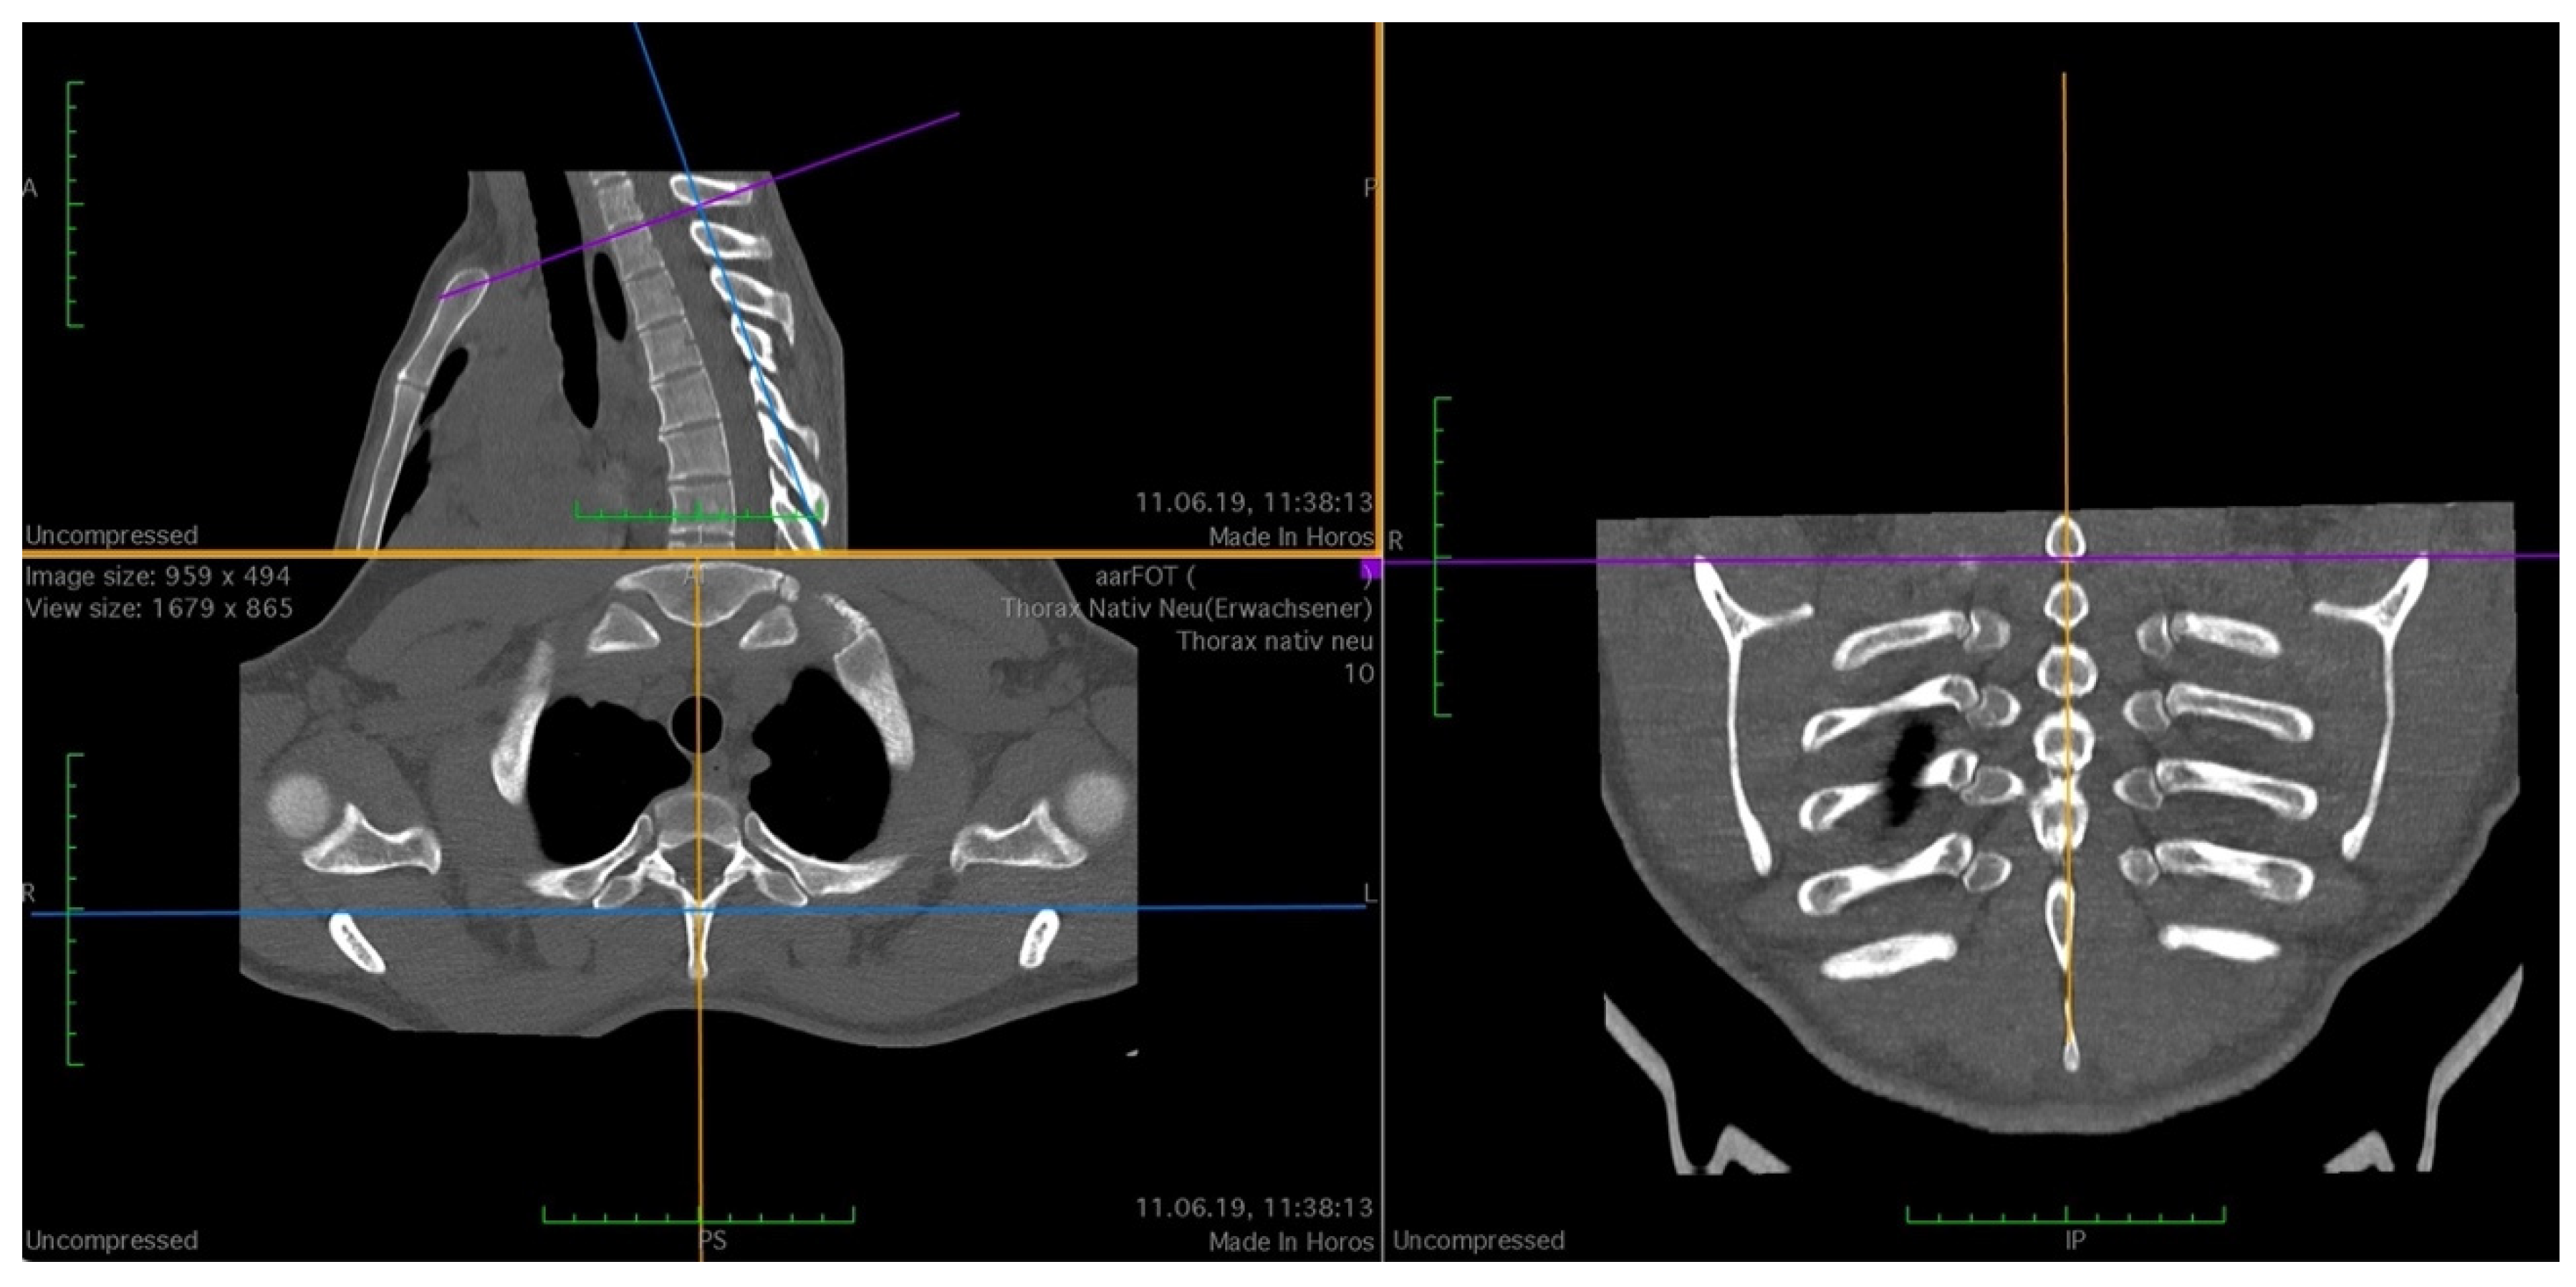

| Variable Name | Abbreviation | Description |

|---|---|---|

| Tuberculum | T | The minimal width of the rib at the level of the tuberculum costae 1 |

| Medial | M | The minimal width of the rib 1 cm medial to the tuberculum costae 1 |

| Lateral | L | The minimal width of the rib 1 cm lateral to the tuberculum costae 1 |

| Rib width | R | Minimal width of the rib at the height of the front edge of the first thoracic vertebral body. |

| Anterior to posterior rip extension | RAP | From the most ventral point of the caput costae 1, a perpendicular line to the tangent of the posterior edge of the first thoracic vertebral body. |

| Vertebral body width | VBW | Width of the first vertebral body at the level of the centre of the articulatio capitis costae 1 |

| Vertebral body depth | VBD | From anterior edge to posterior edge (most ventral point of vertebral foramen) of the first vertebral body |